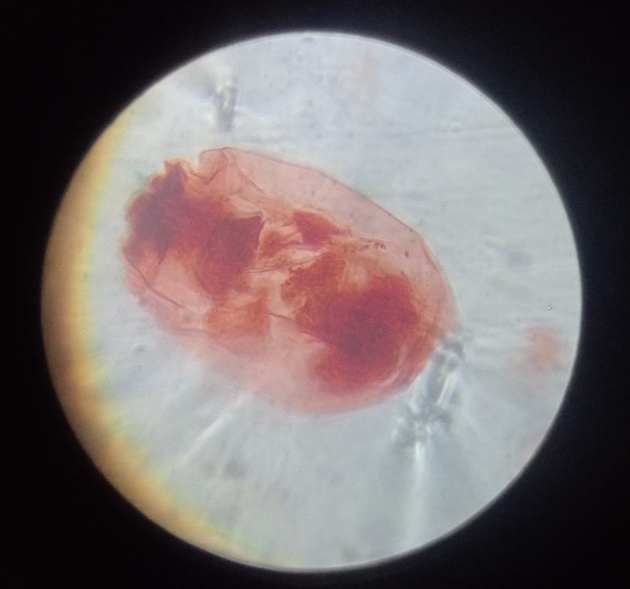

Its name comes from Ancient Greek plásma meaning “something molded” and the suffix -ōdēs meaning “like” or “resembling,” referring to its amorphous, shape-shifting form during its life cycle stages. This etymology reflects the parasite’s ability to adapt morphologically as it transitions between mosquito and vertebrate hosts.

Plasmodium spp. (malaria) in blood smear